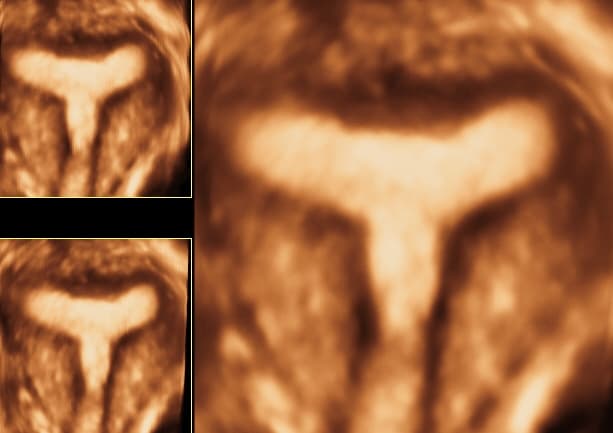

Septirana maternica

Učestalost razvojnih anomalija maternice, koje nastaju uslijed nepravilnog spajanja Müllerovih cijevi i resorpcije u međuvremenu nastalog septuma je u općoj populaciji 5-10%, premda su podatci u literaturi različiti ovisno o karakteristikama skupina žena koje su ispitivane (normalna plodnost, nepodnost, spontani pobačaji).

Septirana ili pregrađena maternica / Uterus septus ili pregrađenu maternicu čine dvije maternične šupljine koje su međusobno odijeljene pregradom u cijeloj duljini ili djelomično (parcijalno septirana maternica). Smatra se da je 15–25% spontanih pobačaja uzrokovano razvojnim anomalijama uterusa, a većina je udružena s nepotpuno ili potpuno septiranom maternicom koja nastaje poremetnjom resorpcije septuma koji nastaje prilikom spajanja Müllerovih kanala. Ovaj tip spontanih pobačaja zbog septiranog uterusa nastaju između 8. i 16. tjedna trudnoće, pretpostavlja se da je uzrok neadekvatna implantacija u području septuma koji je oskudno opskrbljen krvlju. Prerani porod može biti uzrokovan povećanim intrauterinim tlakom s relativnom insuficijencijom vrata materenice, manjkom estrogenskih i progesteronskih receptora u malformiranoj maternici, što može dovesti do abnormalnih kontrakcija uterusa i fetalnog gubitka.

Diferencijalnu dijagnostiku osobito pospješuje primjena trodimenzionalnog i kontrastnog ultrazvuka, kada se u materište instilira fiziološka otopina ili kontrast koja se potom pregledava u svim dimenzijama. Kontrastni ultrazvuk ne samo da je koristan u evaluaciji kongenitalnih anomalija uterusa, već omogućuje i ispitivanje prohodnosti jajovoda. Za trodimenzionalni ultrazvuk se kaže da nalazi uterusa koreliraju s vanjskom konfiguracijom uterusa nađenom pri laparoskopiji, da mu je osjetljivost i specifičnost 100% za dijagnozu velikih anomalija Müllerovih cijevi, i 100% preciznost za bikornualni uterus.